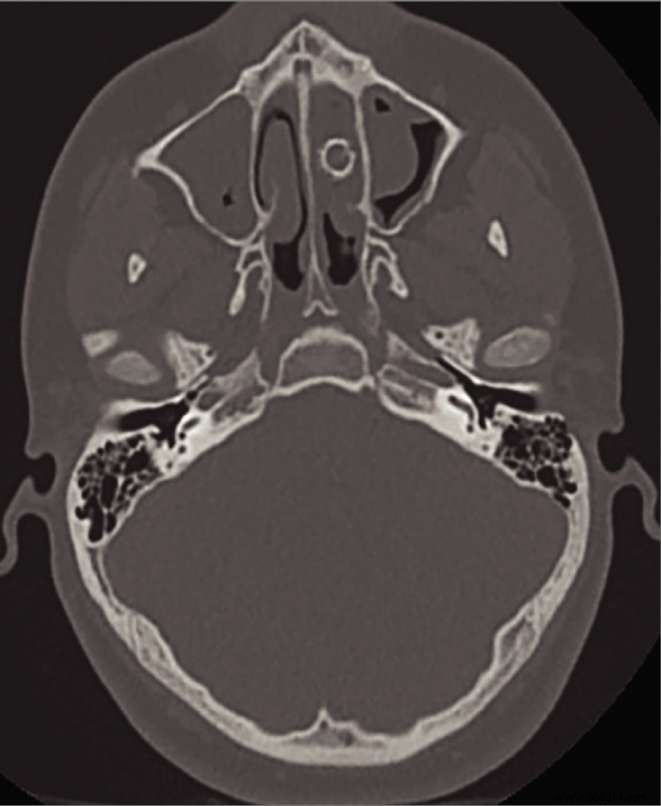

A 15-year-old boy in the United States emitted a foul odor every time he blew his nose. Treating physicians from San Antonio discovered a 9 mm caliber bullet blocking one nasal cavity, which had calcified over time.

Clinicians performed nasal endoscopy, which initially showed no abnormalities. Further investigation revealed a 9 mm diameter bullet in the left inferior nasal cavity. Over time, it had calcified, obstructing natural drainage and trapping debris, bacteria, and mucus—the source of the foul smell.